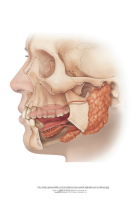

Me võime vaadelda ning sõrmede või keelega katsuda hambaid, keelt, igemeid, huuli, põski, suu lage ja -põhja ning ka neelu, kuid silmale nähtamatuks jäävad hammaste juured, süljenäärmed ning arenevad piima- kui jäävhammaste

alged.